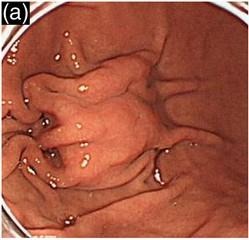

過形成性ポリープは概ね赤色で胃のどの部位にもみられ、大きさは大小様々で、単発の場合もあれば複数みられることもあります。ヘリコバクター・ピロリ陽性で萎縮性胃炎のある胃に発生します。ヘリコバクター・ピロリ除菌治療で、ポリープが縮小もしくは消失することがあります。過形成性ポリープは頻度こそ高くありませんが、大きいものの中で細胞の一部ががん化することがありますので、年1回の内視鏡検査を受けるべきと考えられます。

過形成ポリープはヘリコバクター・ピロリの感染が原因です。ヘリコバクター・ピロリによる胃粘膜の炎症、浅い傷であるびらんや深い傷の潰瘍などの傷が修復される過程で過剰な粘膜の再生によってできるポリープだと考えられています。

過形成性ポリープの症状は通常はほとんどありません。胃の入り口、出口にできた場合、吐き気、胃もたれを起こすことがあります。ポリープが大きくなることにより、食事や胃酸などによる粘膜の刺激で、持続的な出血により貧血をきたすことがあります。一般的にはまったく気が付かずに会社の健診や人間ドックなどで初めてみつかる事がほとんどでしょう。

過形成性ポリープは基本的には経過観察でよいのですが、サイズが大きいだけの場合、まずはヘリコバクター・ピロリの除菌療法を行うことがあります。積極的な内視鏡治療の適応となるのは、大きさ2cm以上で増大傾向を認めるもの、組織検査でがん化(がんの併存)の可能性があるもの、持続的に出血し貧血の原因となる場合で、入院による内視鏡治療による切除(ポリペクトミー、内視鏡的粘膜切除術:EMRや内視鏡的膜下層剥離術:ESD)の適応と考えられます。